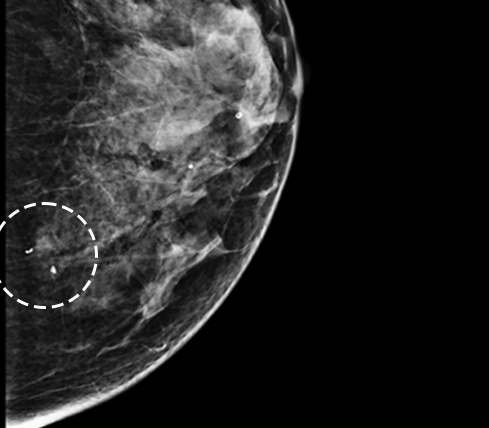

Microcalcification

미세석회화

유방의 석회화는 유방 내 칼슘 성분이 침착된 상태로 유방촬영에서 조직이 하얗게 보입니다. 형태에 따라 양성석회화와 미세석회화가 있습니다.

양성석회화는 유방촬영 시 비교적 큰 석회가 뚜렷하게 보이는 반면 미세석회화는 작은 하얀 점들이 흩어져 있어 보일 듯 말듯 하기도 하고 군집을 이루기도 합니다. 미세석회화 중 20%는 악성(암)이라는 보고가 있기 때문에 모양이 좋지 않거나 추적 관찰 중 변화가 있을 시 조직 검사가 필요합니다.

* 미세석회화: 0.5mm 이하로 작고 단위면적당 입자수가 많으며 크기와 모양이 균일하지 않음